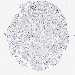

CANCER BREAST CANCER Show tissue menu

BRCA TCGA BRCA VALIDATION PROTEIN EXPRESSION